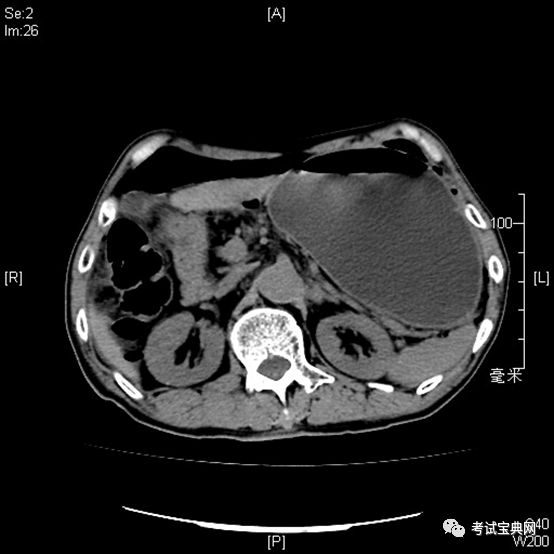

消化道穿孔ct影像大汇总看完印象深刻